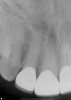

Fig 8. Final periapical radiographs of the restorations prior to delivery. The marginal integrity interproximally is evaluated to ensure adequate seating of restorations and closed margins.

Figure 8

Fig 9. Final periapical radiographs of the restorations prior to delivery. The marginal integrity interproximally is evaluated to ensure adequate seating of restorations and closed margins.

Figure 9